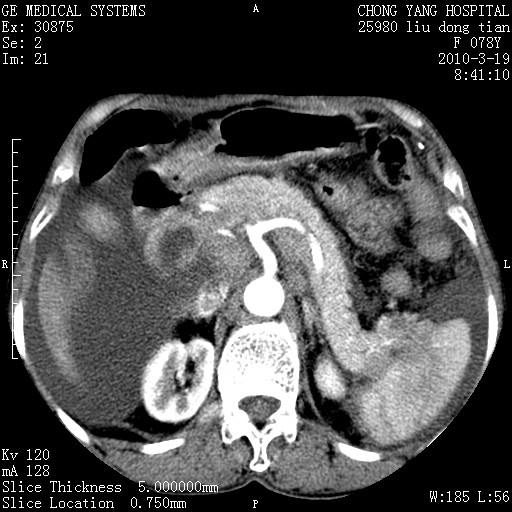

标题: CT25199:F 78Y 腹胀半年 消瘦乏力 [打印本页]

胆囊壁增厚并明显强化,胆囊癌伴多发转移瘤可能性大,淋巴瘤不除外,右肾囊肿,胸腹水.

考虑nhl,肝、脾、腹膜腔及腹膜后多发淋巴结受侵,腹水,右肾囊肿,慢性胆囊炎,右侧少量胸腔积液。

胰头有肿块形成,胰头ca伴肝脾、腹膜腹膜后转移

胆囊有软组织影有强化,支持胆囊癌,肝脾、腹膜后淋巴结转移。

nhl的淋巴结多围绕主动脉,而且主动脉会移位,所以不考虑nhl。

分开来讲:肝左叶、尾叶病灶有不均强化像肝癌;

脾脏病灶无强化,像多发囊肿或淋巴管瘤,不除外淋巴瘤(低强化);

胆囊增生性病变:胆囊癌,腺肌增生症,慢性胆囊炎;

肝门、胰腺头、腹膜后多个团块: 淋巴瘤,转移;

腔静脉肝内段细小有无布加可能?

一元论最好了 淋巴瘤所致改变; 胆囊癌转移不像,胆囊周围肝组织清晰,肝癌淋巴结转移?三元论都不止。

最后报的胰头癌多发转移,脾脏单独考虑囊肿或淋巴管瘤。